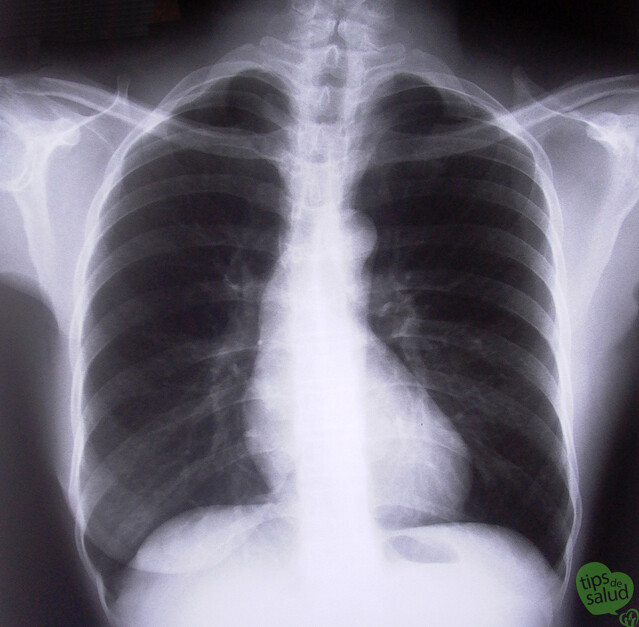

Problemas pulmonares

Neumonía

Neumotórax

Derrame pleural